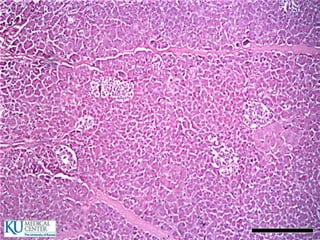

Glándulas salivales principales

 Glándula parótida

 Glándula submaxila

 Glándula sublingual